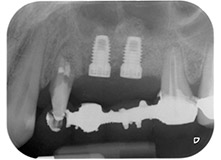

Un mes después, en el día de la intervención, el dolor y la inflamación se habían reducido al mínimo en la pieza 24, pero seguía habiendo una movilidad de clase II de Miller. Después de la apertura de los colgajos y de la limpieza del tejido infectado periapical y perirradicular, la extensión del defecto óseo quedó evidente (figuras 2 y 3).

En la raíz bucal, faltaba todo el hueso vestibular y distal. Básicamente, la fijación se limitó a la raíz palatal, lo que corroboró el mal pronóstico preliminar. La pieza 27 también mostró una fijación horizontal reducida (figura 12) y una rarefacción apical mínima (figura 1), si bien sin síntomas clínicos.

A pesar de todo, confirmamos nuestro plan inicial de conservar ambas piezas dentales como pilares de puente provisionales durante el período de osteointegración de los implantes, que duraría 6 meses. En el momento de la reanudación del tratamiento, la situación tendría que volver a evaluarse.